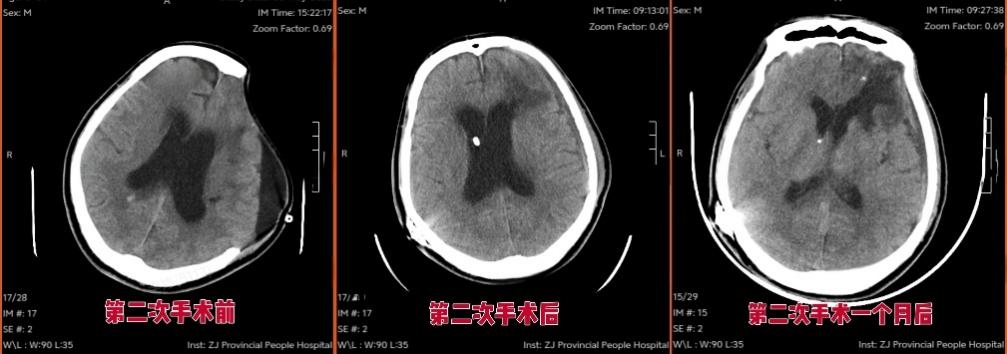

“必须再次手术!”

然而,王先生这一路并没有一帆风顺。颅骨缺损后骨窗凹陷明显,出现了脑积水问题,肢体活动、认知言语功能恢复缓慢,反应迟钝,坐不稳站不稳,仍然没有生活自理能力……

面对康复中遇到的“硬骨头”,脑血管意外康复病区联合神经外科团队制定“手术+康复”接力方案:由神经外科再次为王先生实施颅骨修补术,来稳定颅内结构,消除骨窗凹陷,此外进行脑室腹腔分流术,解决脑积水问题,为神经修复扫清障碍。